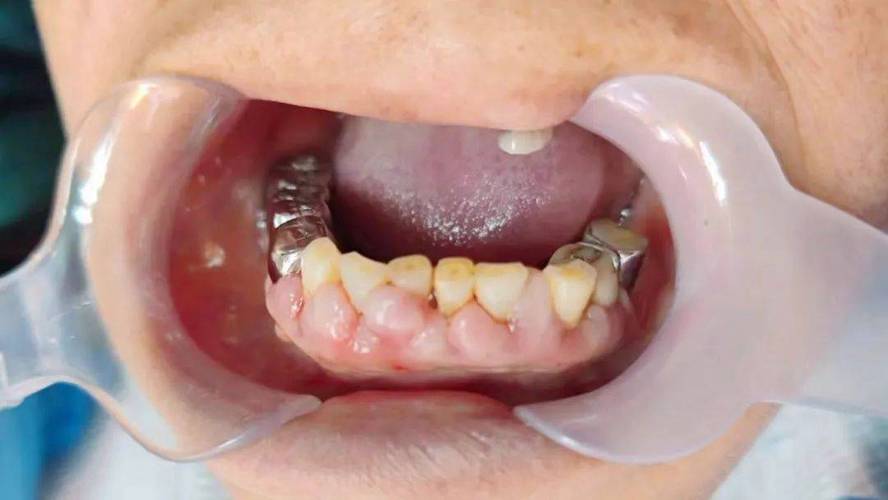

🔍 二、牙龈增生的表现

- 牙龈肿胀、肥大: 牙龈组织体积明显增大,可能覆盖部分牙面(尤其是牙齿颈部)。

- 质地改变: 早期可能松软、易出血;慢性或纤维化增生时质地变韧、变硬。

- 颜色改变: 呈鲜红色或暗红色,牙龈乳头(牙缝处的牙龈)呈球状增生。

- 易出血: 刷牙、进食甚至触碰时容易出血。

- 影响美观: 增生的牙龈可能影响笑容美观。

- 影响口腔功能: 严重时可能影响发音或清洁。

- 可能影响正畸效果: 增生的牙龈可能包裹托槽,影响弓丝入槽,或阻碍牙齿移动到理想位置。